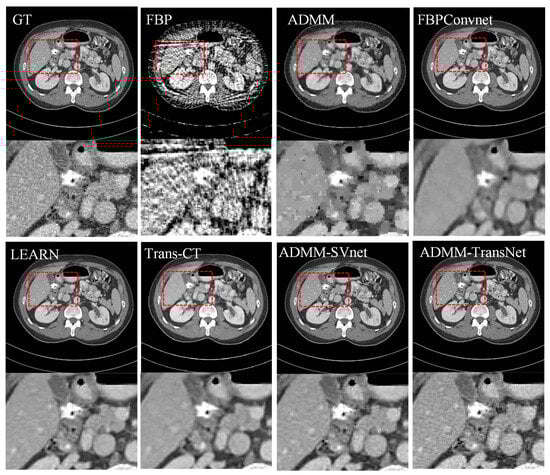

4.1. Simulation Data Research

| Views | 128 | 64 | 32 | ||||||

|---|---|---|---|---|---|---|---|---|---|

| Metric | PSNR | SSIM | MAE | PSNR | SSIM | MAE | PSNR | SSIM | MAE |

| FBP | 26.140 | 0.808 | 0.044 | 22.067 | 0.612 | 0.074 | 18.935 | 0.539 | 0.126 |

| ADMM | 33.751 | 0.929 | 0.021 | 30.883 | 0.915 | 0.027 | 29.753 | 0.907 | 0.038 |

| FBPConvNet | 39.854 | 0.952 | 0.020 | 34.243 | 0.938 | 0.028 | 30.648 | 0.916 | 0.035 |

| LEARN | 42.972 | 0.975 | 0.009 | 39.943 | 0.977 | 0.012 | 36.935 | 0.938 | 0.019 |

| Trans-CT | 40.877 | 0.966 | 0.011 | 35.855 | 0.941 | 0.019 | 32.430 | 0.922 | 0.023 |

| ADMM-SVnet | 43.229 | 0.995 | 0.007 | 42.974 | 0.989 | 0.008 | 40.212 | 0.972 | 0.013 |

| Ours | 44.633 | 0.996 | 0.006 | 43.726 | 0.992 | 0.007 | 42.036 | 0.979 | 0.011 |